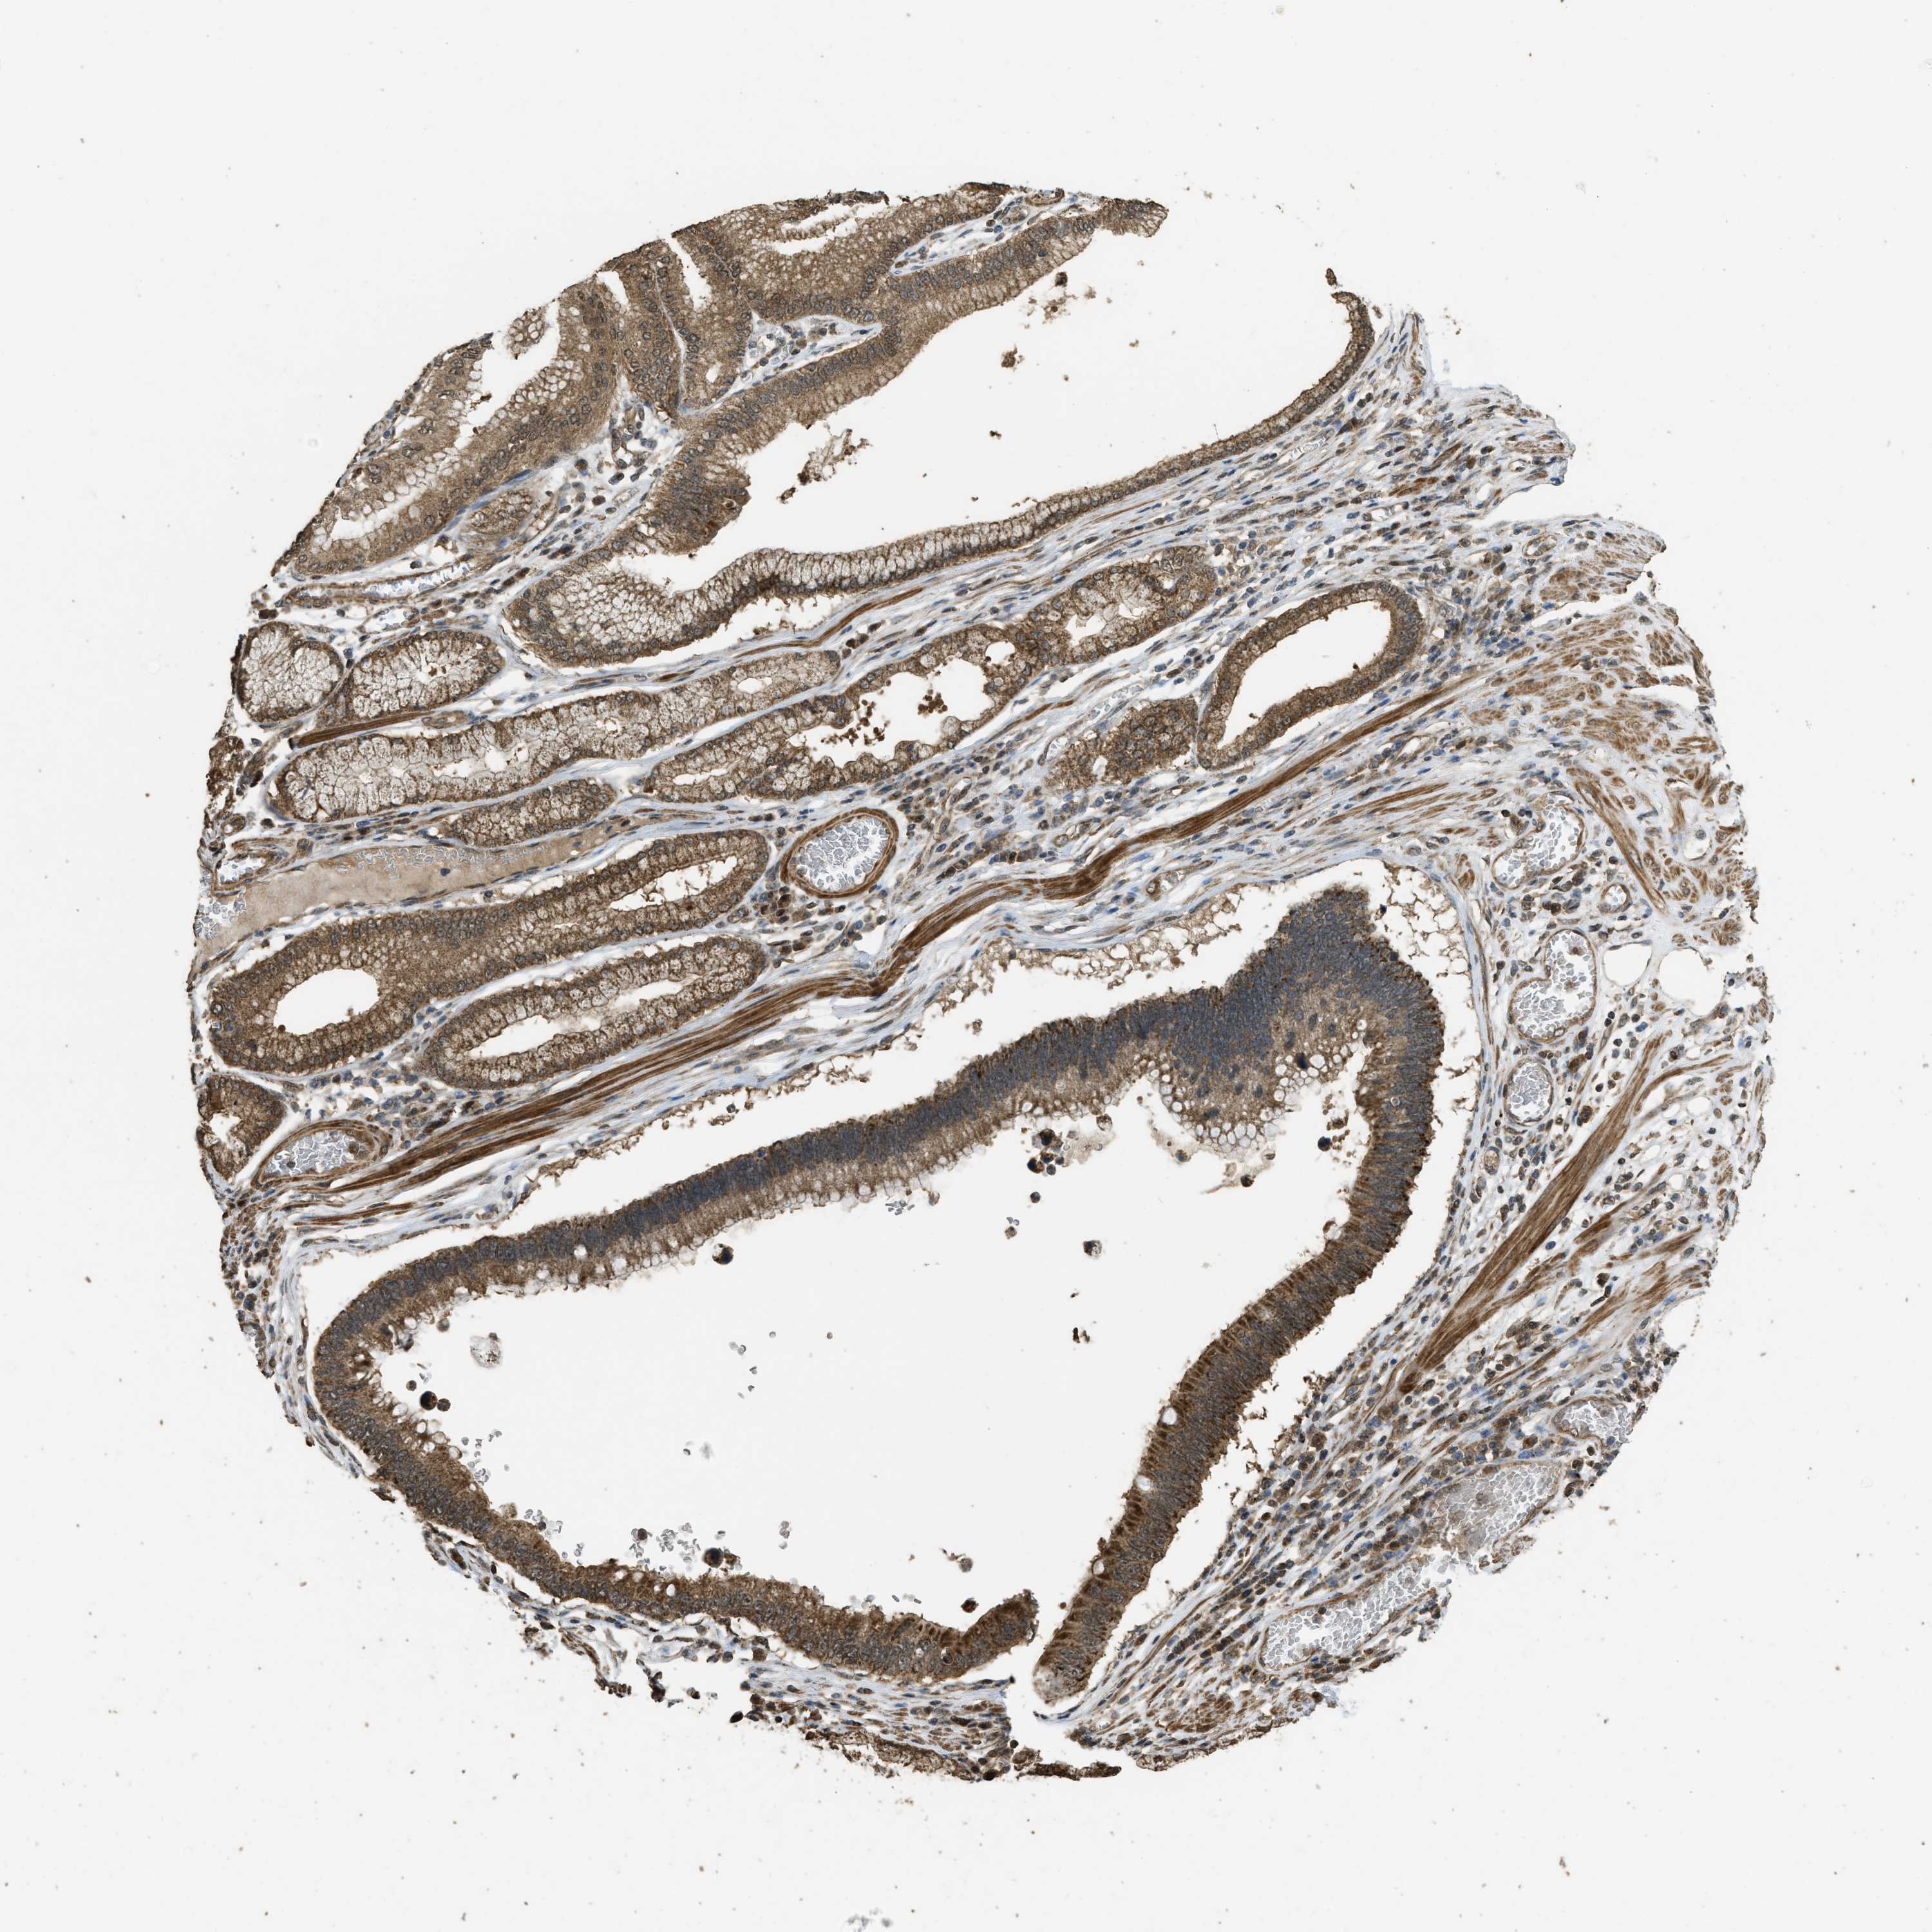

STOMACH CANCER - Protein expressioni

A mouse-over function shows sample information and annotation data. Click on an image to view it in a full screen mode. Samples can be filtered based on level of antibody staining by selecting one or several of the following categories: high, medium, low and not detected. The assay and annotation is described here.

Note that samples used for immunohistochemistry by the Human Protein Atlas do not correspond to samples in the TCGA dataset.

Antibody stainingi

Antibody staining in the annotated cell types in the current human tissue is reported as not detected, low, medium, or high, based on conventional immunohistochemistry profiling in selected tissues. This score is based on the combination of the staining intensity and fraction of stained cells.

Each image is clickable and will lead to virtual microscopy that enables deeper exploration of all samples and also displays staining intensity scores, fraction scores and subcellular localization as well as patient and tissue information for each sample.

Antibody HPA051322

Antibody CAB017111

Staining

High

Medium

Low

Not detected

Intensity

Strong

Moderate

Weak

Negative

Quantity

>75%

75%-25%

<25%

None

Location

Nuclear

Cytoplasmic/membranous

Cytoplasmic/membranous,nuclear

Adenocarcinoma, NOS

Adenocarcinoma, High grade